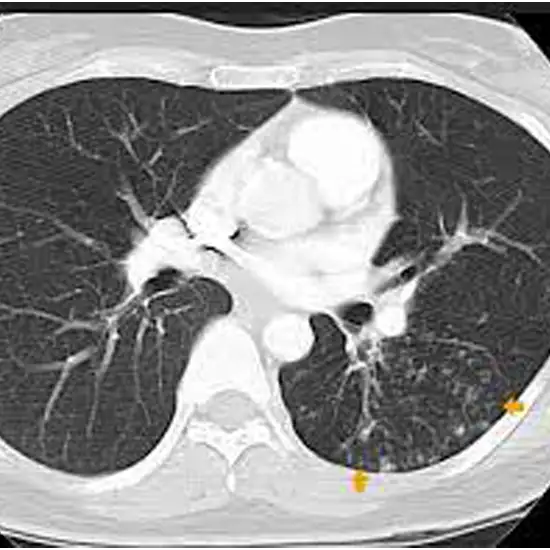

NCCT thorax (Non-contrast computed tomography of the thorax ) is a plain study of the thorax to visualize the internal structure and pathology(disease condition) of the thorax. It is used to see the infection, inflammation, fractures, injuries or cancers in the thorax cavity and the surrounding area.

NCCT thorax is performed in a CT scanner, the patient is advised to lie supine on the table attached to the scanner and the arm is placed on the sides. The table slides into the scanner, which is a doughnut-shaped machine. Patients need to limit their movement, remain still and hold their breath for 15 to 20 seconds to get more clear and detailed images as the movement can blur the images. NCCT thorax takes around 10-15 minutes to complete.

NCCT thorax is a plain study used to evaluate structures and abnormalities of the thorax region. The scan helps in producing scan images that replicate the internal structures as it is, the visualisation helps determine associated pathology and disease conditions in the thorax region.

NCCT thorax test scan shows inflammation, infection, fractures, injuries, dislocation, tumours etc. in the thorax.